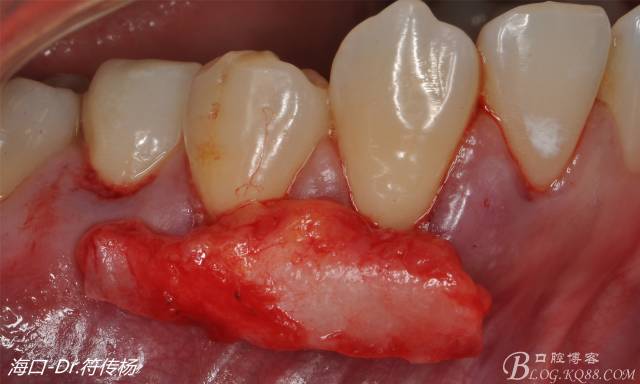

確定取出結(jié)締組織長度是否適當(dāng)

腭部使用水平懸吊縫合更利于壓迫止血

受植區(qū)建議使用雙交叉垂直懸吊縫合術(shù)來固定結(jié)締組織并能讓齦瓣更貼合根面利于術(shù)后一期愈合